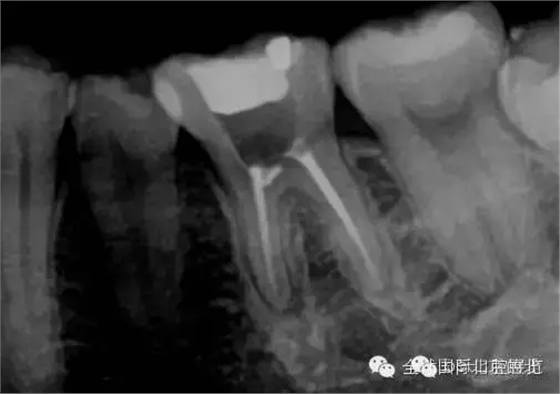

常規(guī)X-RAY全景片檢查

我們再來看看患牙:

X-RAY示:近遠中牙根都有陰影存在,牙周膜都有些許增寬,近中頸部位置牙體有低密度減低影,就是楔狀缺損的位置。 病因分析:楔狀缺損的深齲致牙髓壞死引起的根尖炎癥,應囑患者以后改變刷牙方式 診斷:36慢性根尖炎急性發(fā)作 治療方案:36做根管治療,然后充填完成后行冠修復。 首次治療過程:開髓引流,無明顯滲出液,pathfile疏通根管,沖洗,氫氧化鈣暫封,一周復查。